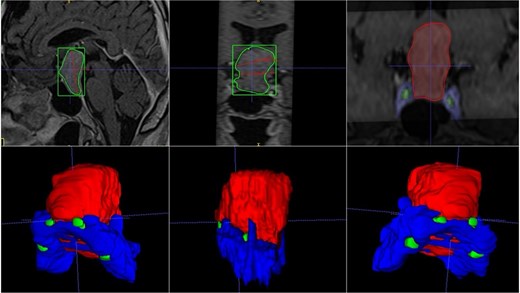

A 42-year-old patient who suddenly presented with headache and visual disturbances. The examination confirmed bitemporal hemianopsia, as well as bilateral papilledema. An MRI study obtained the following sequences: T1, T2, and T1 with contrast (Fig. 4). Manual 3D segmentation was performed to observe the intratumoral components and classify the different anatomical portions of the tumor, as well as its total estimated tumor volume and area (Fig. 5 and Table 2). The importance of reconstruction, in this case, lay in knowing the areas that were possibly not going to be so easily accessible through this endoscopic approach, as well as in calculating the volume of the tumor per segment and the possibility of having residual tumors in less accessible segments.

Contrast-enhanced T1 MRI of pituitary marcoadenoma. Multiplanar conventional geometric volumetry.

Manual planimetric volumetric segmentation. (A) Calculation of total tumor volume (red) and its relationship with the internal carotid artery (green). (B) Volumetry by zones. (C and D) Areas shown in sagittal and coronal planimetry.

| Geometric volumetry . | 3D volumetry . | Zone 1 Red (Intraspenoidal) . | Zone 2 Green (Intercarotid) . | Zone 3 Blue stronge (Supracarotid suprasellar) . | Zone 4 Yellow (Retrocarotid intraselar) . | Zone 5 Blue clear (Supraselar retrocarotid) . |

|---|---|---|---|---|---|---|

| 16 cubic centimeters | 21 cubic centimeters | 1.7 cubic centimeters | 3.7 cubic centimeters | 2.3 cubic centimeters | 9.7 cubic centimeters | 3.6 cubic centimeters |

The above is similar to our case number two, where the tumor is quite irregular in conventional ABC/2 volumetry; the real volumetric value of the tumor is underestimated; however, with our manual segmentation, the volumetry can even be measured by zones. In that case, it was important to measure the area where there was a greater possibility of residual tumor and thus be able to correlate it with the possibility of greater rates of total resection.